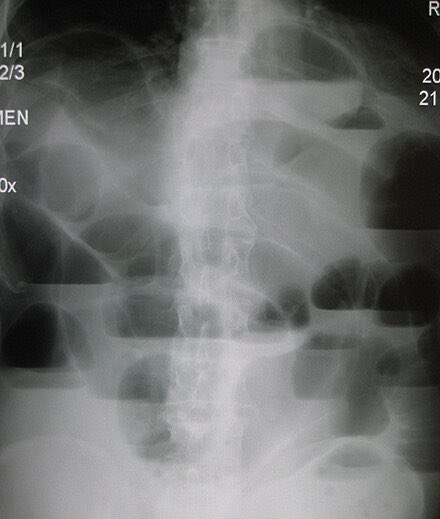

🚨 Thread: Radiology in Common Emergencies 🚨1/x #Medtwitter #radiology #Emergency potential #neetpg questions